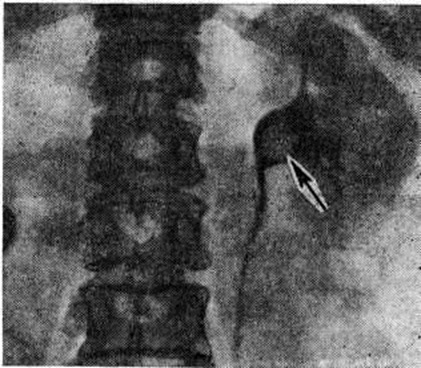

Рис. 4.

Экскреторная урограмма: рентгенонегативный камень в лоханке левой почки (указан стрелкой), дефект наполнения с чёткими контурами.

Рентгенологические метод является основным в диагностике Почечнокаменная болезнь Он позволяет выявить не только наличие камней, но и установить их форму, величину, локализацию, структуру, а также получить представление об изменениях в анатомо-функциональном состоянии почек и мочевых путей. Исследование начинают с обзорной рентгенографии брюшной полости, начиная от ThXl до лонного сочленения. Обнаружение на обзорной рентгенограмме тени, подозрительной на конкремент, не требует дифференциальной диагностики только в случае коралловидного камня, являющегося слепком чашечно-лоханочной системы (рисунок 2). Камни почечных чашечек представляют собой их слепки или имеют неправильную, округлую форму; камни почечной лоханки часто округлые или треугольные; камни мочеточника — цилиндрической, веретенообразной или неправильной формы. При аномалиях мочевых путей конкремент может находиться вне обычной локализации почек и других органов мочеполовой системы. Обнаружение камня на снимке зависит от его размеров, химический состава и локализации. Наиболее интенсивное изображение дают оксалаты, затем камни смешанного состава и фосфаты. Оксалаты имеют шиповидные, фестончатые контуры и напоминают тутовую ягоду. Коралловидные камни чаще всего компактны, но могут быть слоистыми, как и остальные конкременты смешанного состава, иногда они достигают гигантских размеров. Слоистое строение камней на рентгенограммах обусловлено различной проницаемостью для рентгеновского излучения составляющих их солей. Около 10% камней с низким атомным весом (ураты, белковые, цистиновые и ксантиновые камни) не видны или дают неотчётливую тень. Особенно трудно выявить камни, проецирующиеся на костный скелет (ребра, поперечные отростки позвонков, крестцово-подвздошные сочленения). Для их обнаружения производят прицельные снимки в косых и атипичных проекциях, томо или зонографию. Томография (смотри полный свод знаний), применяемая самостоятельно или в сочетании с контрастными исследованиями, показана при недостаточной подготовке больного к рентгенологическое исследованиям, почечной колике, сопровождающейся парезом кишечника, или при малых размерах камней. Поскольку при Почечнокаменная болезнь довольно часто конкременты самопроизвольно отходят из чашечно-лоханочной системы, они могут проецироваться по ходу мочеточника паравертебрально, имеют тенденцию задерживаться над одним из его анатомических сужений. Наиболее важные сведения о принадлежности выявленной тени к мочевым путям, о локализации камня, вызванных им нарушениях функции почек, уродинамики, анатомического состояния мочевых путей (гидрокаликоз, пиелэктазия, гидроуретеронефроз — расширение чашечек, лоханки, мочеточника и почки) выявляются при экскреторной урографии (рисунок 3, б) с предварительной обзорной рентгенографией (рисунок 3, а). Она позволяет установить вид лоханки (открытая или закрытая, внутрипочечная или внепочечная), состояние лоханочно-мочеточникового сегмента (смотри полный свод знаний: Пиелография). Обычно рентгенопозитивный конкремент определяется в мочевых путях, но иногда его изображение перекрывается, как бы тонет на фоне контрастированной мочи, особенно при небольшом камне или малой интенсивности его изображения. При рентгенонегативных камнях виден дефект наполнения мочевых путей (в том числе и лоханки) с чёткими контурами (рисунок 4). В отличие от опухоли лоханки в косых проекциях вокруг камня сохраняется ободок контрастного вещества. Обычно при камнях лоханки, достигающих в диаметре 3 сантиметров и более, наблюдаются пиелэктазия и гидрокаликоз. Произведённые в процессе экскреторной урографии телевизионная пиелоуретероскопия в сочетании с кинематографией или видеомагнитофонной записью изображения позволяют оценить нарушения тонуса и моторной функции верхних мочевых путей при камнях, отличить спастические, функциональный процессы от органических. Если спустившийся в мочеточник камень частично закрывает его, то отмечаются расширение мочеточника и лоханки (пиелоуретерэктазия) выше уровня расположения конкремента. На экскреторных урограммах, произведённых во время почечной колики, выявляется увеличенная почка с усиленным нефрографическим эффектом без контрастирования чашечно-лоханочной системы и мочеточника — так называемый большая белая почка. Такая рентгенологическое картина указывает, что функция почки сохранена. При длительной полной блокаде камнем (более 3—4 недель) функция почки из-за атрофии снижается и может полностью утрачиваться. На экскреторных урограммах, произведённых после почечной колики, иногда наблюдается проникновение контрастированной мочи за пределы мочевых путей, а также лоханочно-почечный рефлюкс. Ретроградную пиелоуретерографию с жидким контрастным веществом или кислородом производят только при значительном снижении функции почек, при сомнении в диагнозе, особенно в тех случаях, когда при экскреторной урографии не выявляется рентгенонегативный камень. Рентгенографию мочеточника после введения в него катетера производят в прямой и косой проекциях. Если при этом тень, подозрительная на камень, на обоих снимках находится рядом с катетером или сливается с его тенью, то диагноз Почечнокаменная болезнь не вызывает сомнений. Тень, не относящаяся к мочеточнику, определяется на некотором расстоянии от катетера. На ретроградных пиелограммах с жидким контрастным веществом небольшой концентрации рентгенонегативные камни выявляются в виде дефекта наполнения. Особенно демонстративными такие камни становятся при пневмопиелорентгенографии или пневмопиелотомографии (рисунок 5). С помощью ретроградной уретерографии удаётся выявить рентгенонегативный камень в мочеточнике, верхние границы дефекта при этом имеют вогнутую форму (рисунок 6).